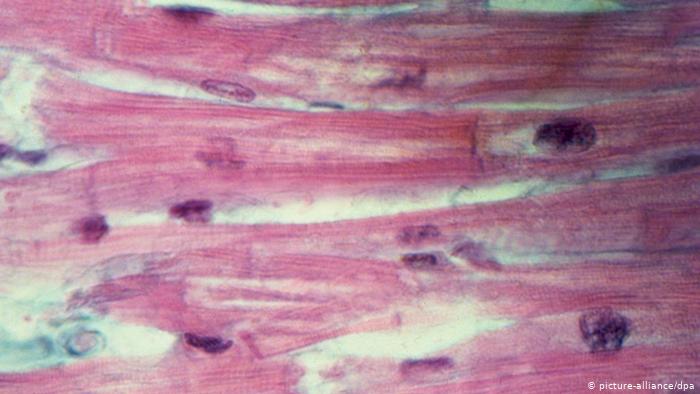

القلب هو عبارة عن عضلات من نوع خاص تشبه العضلات الموجودة في اليدين أو الساقين من حيث سرعة وقوة تقلصها. ولكن الذي يميز عضلات القلب عن غيرها هو قابليتها للعمل لفترة طويلة بدون تعب أو كلل. بالإضافة إلى ذلك فان خلايا نسيج عضلة القلب ترتبط مع بعضها البعض مشكلة شبكة كبيرة، كما يظهر في الصورة، والتي تساعد القلب على العمل كعضلة واحدة أثناء النبض.